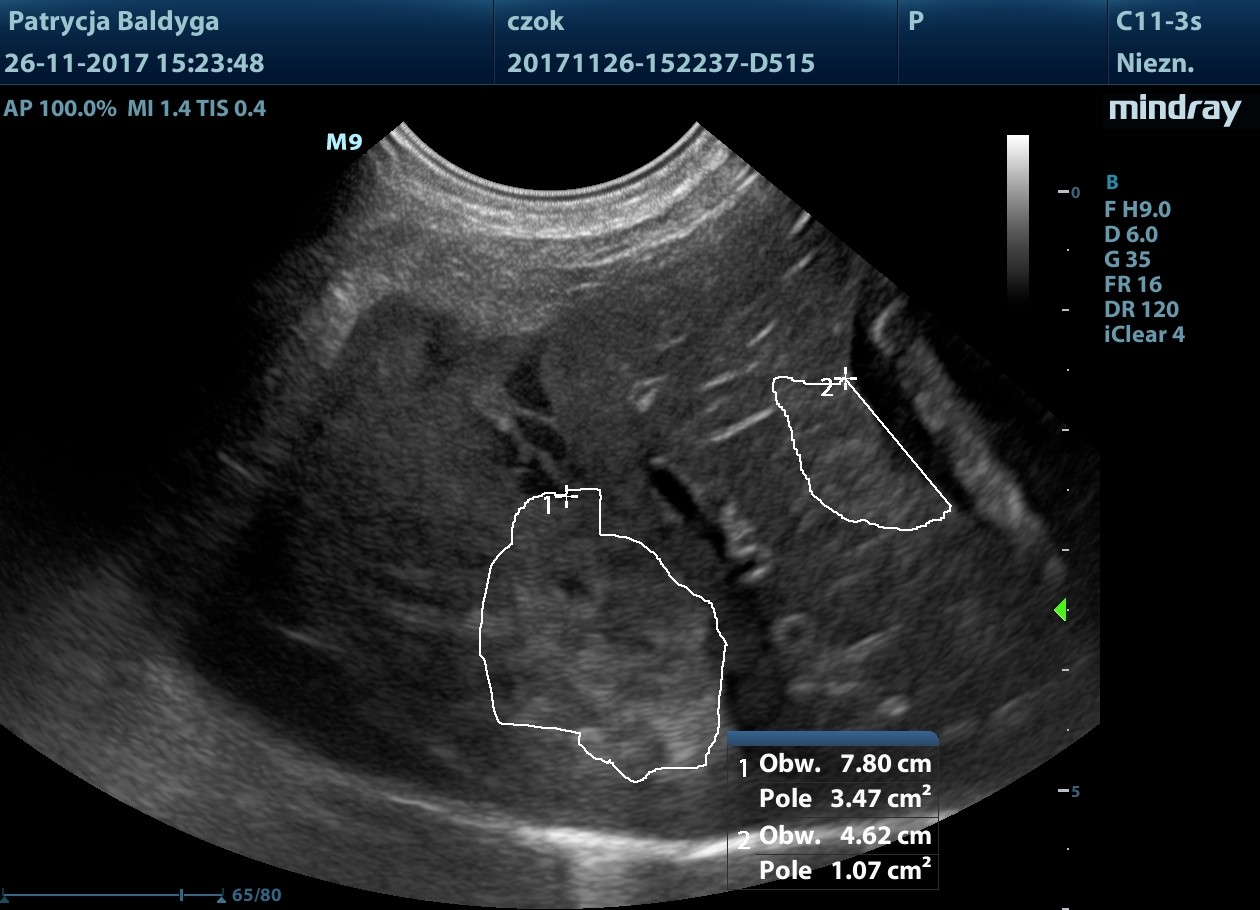

Obecność znacznie zwiększonych ilości wolnego, nieco zagęszczonego płynu w jamie otrzewnej, widocznego w dużej ilości przypęcherzowo, przywątrobowo, pomiędzy pętlami jelit oraz śladowo również w przestrzeni zaotrzewnowej

- co nasuwa duże podejrzenie krwotoku masywnego, najpewniej z wątroby, wskazanie do laparotomii zwiadowczej.